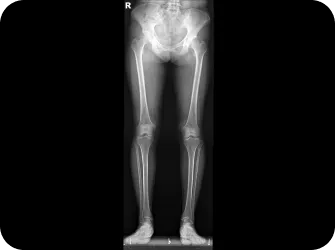

발은 우리 몸에서 건물의 주춧돌과 같은 역할을 합니다. 발의 틀어짐으로 인한 통증은 단순히 발의 문제로 그치지 않고 보행 패턴을 무너뜨리며 다리와 무릎 관절, 나아가 골반과 허리의 추간판까지 연쇄적인 영향을 미칩니다. 발의 문제를 조기에 발견해 치료하는 것이 전신 건강을 위해 중요합니다.

하루에 매번 320KM 속도로 지면에서 올라오는 충격과 하루 600t 의 부하를 견디는 발은 충격을 더 많이 흡수 할 수 있는 구조로 진화 해왔습니다.

▲ 발의 문제로 인해 생기는 요통

발이 몸의 2%만을 차지하면서도 98%의 체중을 지탱할수 있는 이유는 바로

체중을 지혜롭게 분산시키는

아치(Arch)가 있기 때문입니다.

따라서 발의 아치가 무너지면 체중과 지면의 충격이

특정 부위로 쏠리면서

다양한 발 질환이 생기게 됩니다.

척추와 골반이 틀어지면 체중이 고르게 분산되지 않고 보행 패턴도 불균형해져서 한쪽 발에 과도한 부담이 집중됩니다. 여기에 척추 디스크나 협착증으로 인한 신경 압박은 발의 통증을 더욱 악화시키는데, 특히 노화로 엉덩이 근육이 약해지면서 통증이 가속화 되는 경우가 많습니다. 발 질환의 효과적인 치료를 위해서는 척추와 골반을 바로 잡아 양발에 체중이 균등하게 분산되도록 하는것이 중요합니다.

무릎의 변형을 발질환에 많은 영향을 미칩니다.

O 다리나 X 다리 , 무릎이 뒤로 밀려난 슬관절과신전 패턴 등은 보행패턴을 망가뜨리고 정상적인 보행을 방해하여 발질환을 만성화시키는 주 원인이 됩니다.